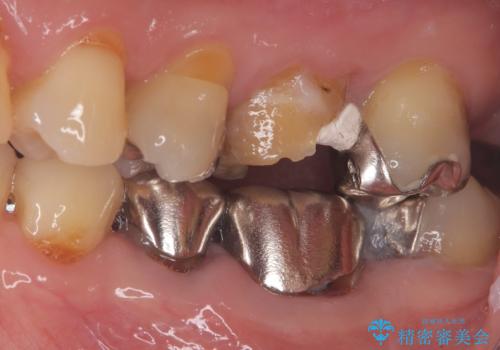

- 患者様は、他院で根管治療を受けていたが、なかなか治らず、より精密な治療を希望して当院を受診されました。マイクロスコープを使用して詳しく診断したところ、上顎第一大臼歯(6番)のMB2(第二頬側根管)の見落としが判明。このままでは感染が残り、再発のリスクが高い状態であるため、当院で精密根管治療を行う方針としました。

マイクロスコープを使用してMB2を確認し、感染源を徹底的に除去。その後、根管内を清掃・消毒し、高品質な充填材で密閉しました。従来の根管治療では見落とされがちなMB2の発見により、治療の精度が大幅に向上し、炎症の改善が期待できる状態となりました。患者様からは「治療後の違和感がなくなり、しっかり噛めるようになった」と喜びの声をいただきました。